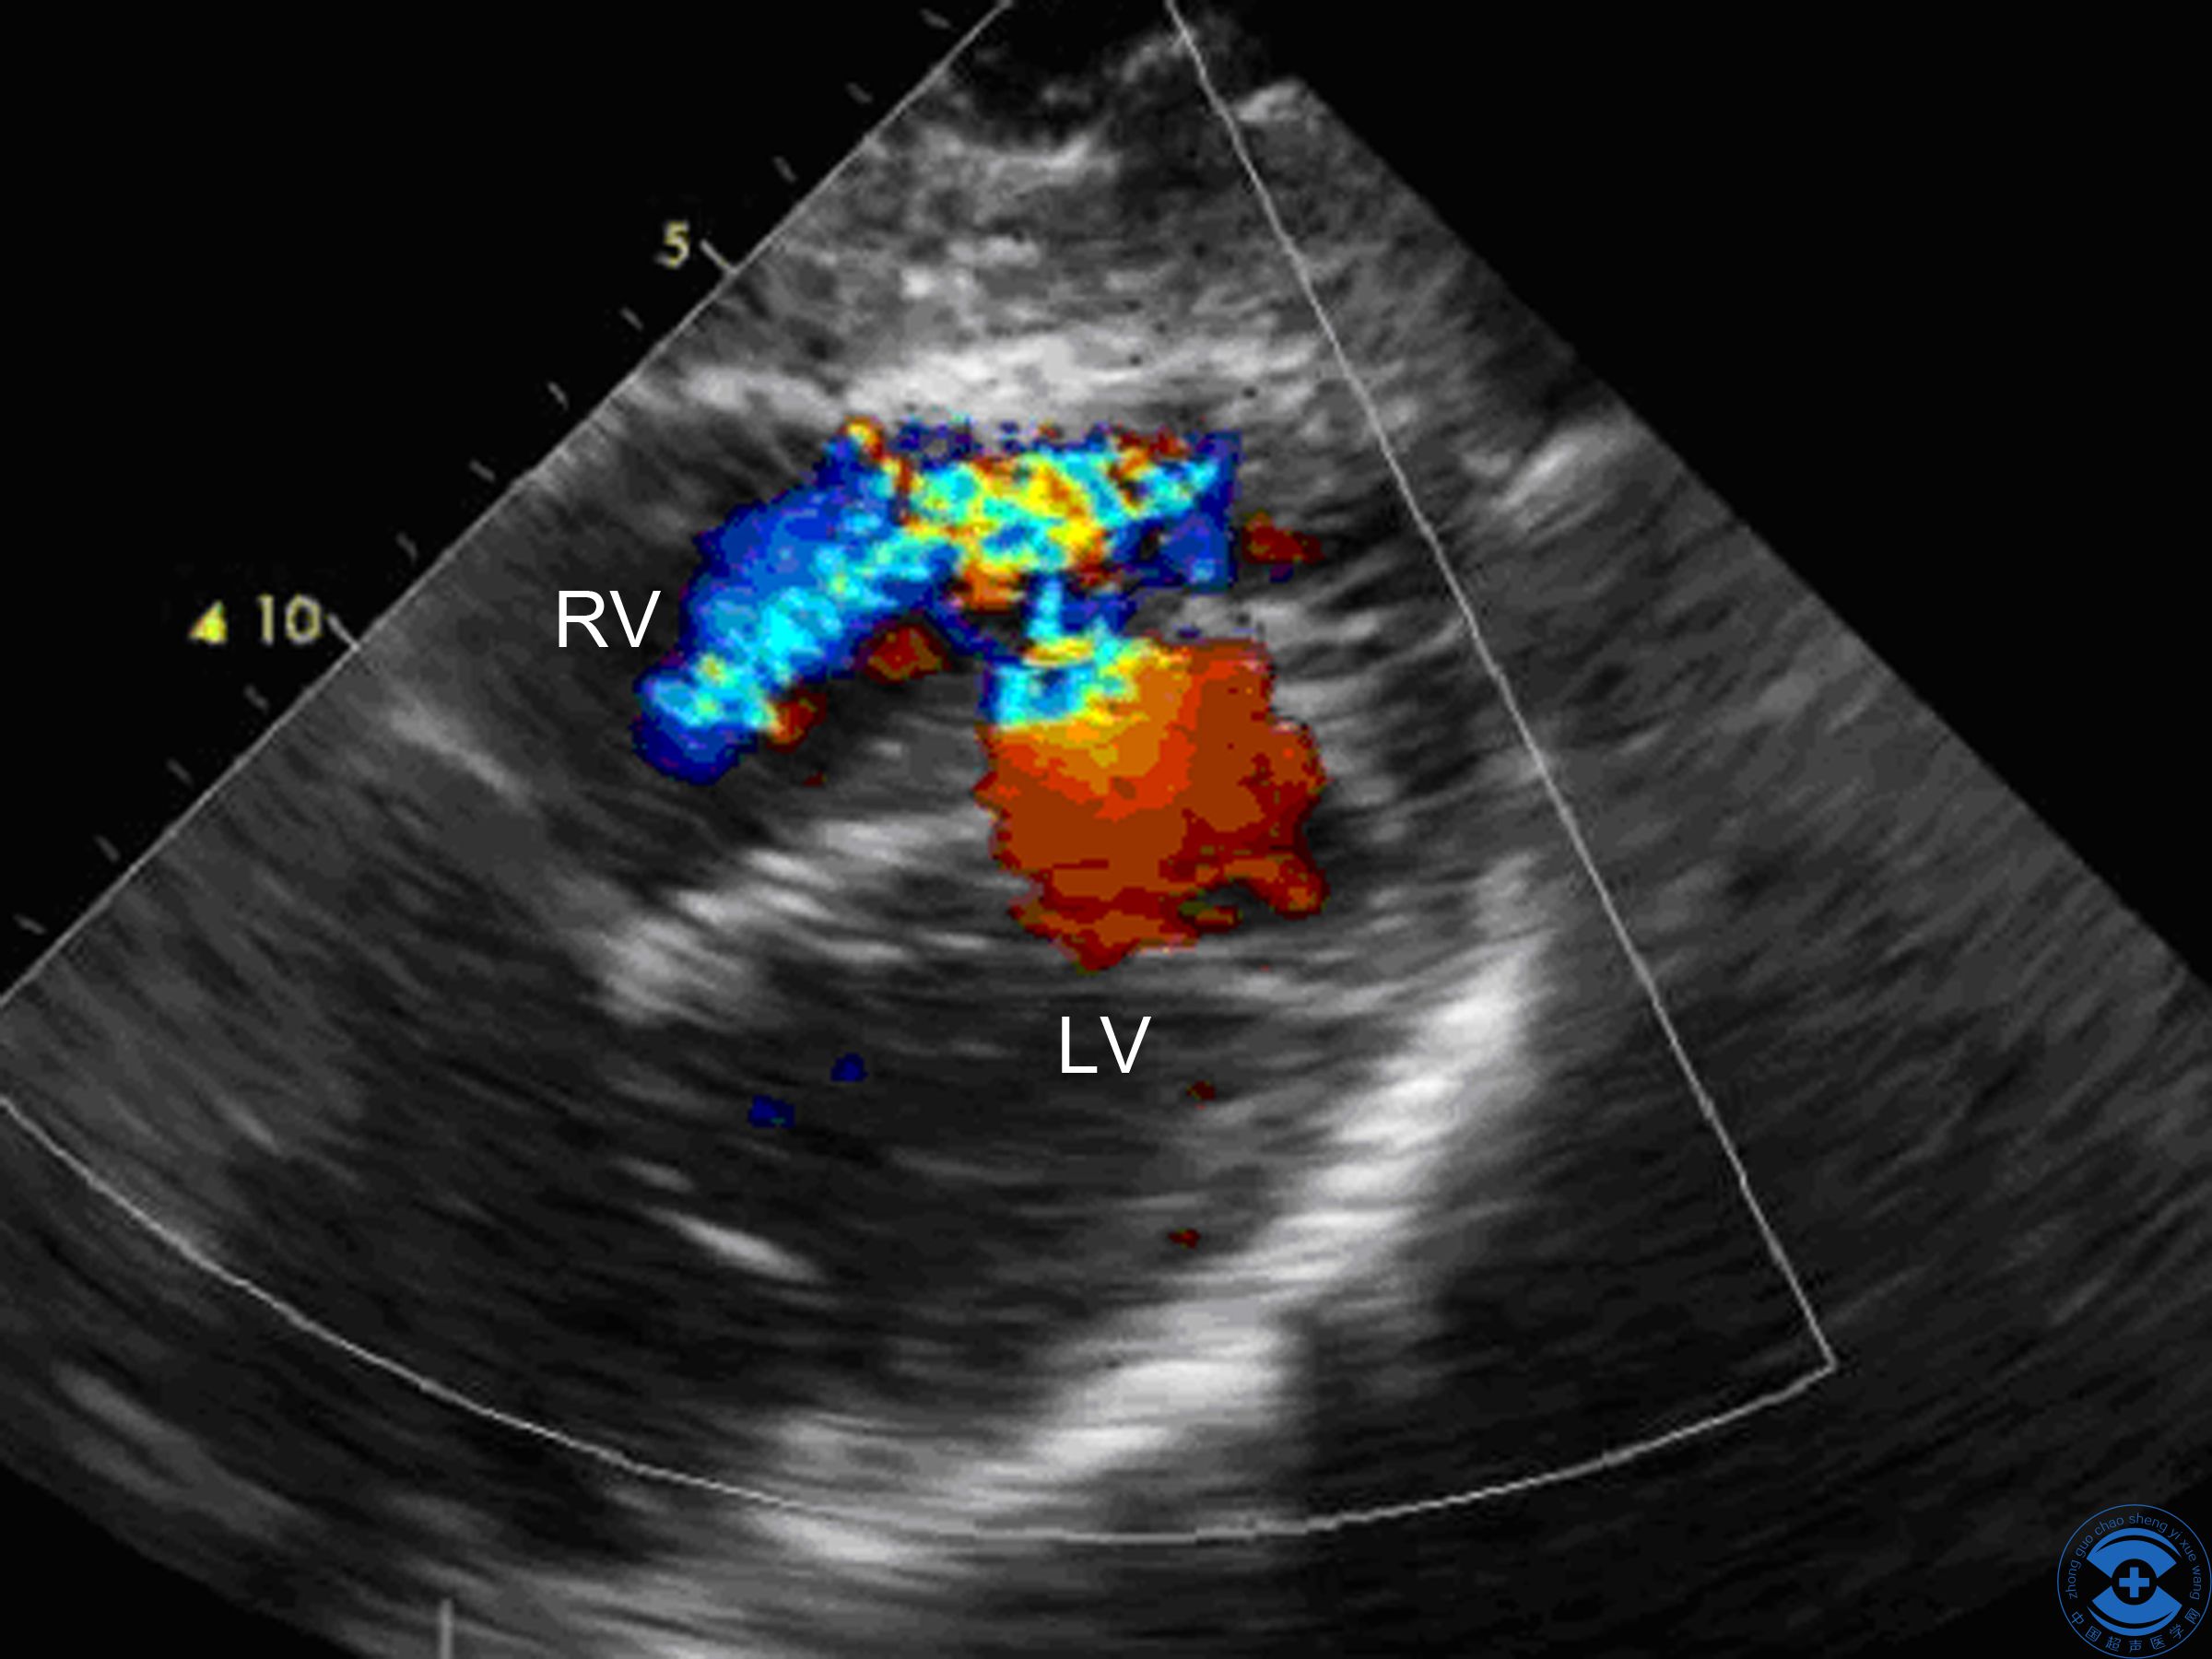

图4 心室水平分流:术前剑突下切面显示室水平分流